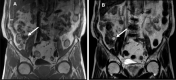

Case presentation: A 72-year-old male was referred to our hospital to examine the cause of hematochezia. A colonoscopy study showed a protruding lesion resembling a submucosal tumor (SMT), approximately 20 mm in diameter, at the site around the appendiceal orifice of the cecum. An abdominal computed tomography and magnetic resonance imaging showed a cystic lesion at the appendiceal base. The lesion was clinically diagnosed as a cystic tumor of the appendix, but the possibility of a malignant tumor could not be excluded. Therefore, a laparoscopic ileocecal resection with lymph node dissection was performed. The pathological examination of the resected specimen revealed that the lesion was a diverticulum (pseudodiverticulum) occurring solitarily at the appendiceal base, in which the mucosal layer of the appendix was invaginated into the submucosa of the adjacent cecum, thus forming an SMT-like lesion.